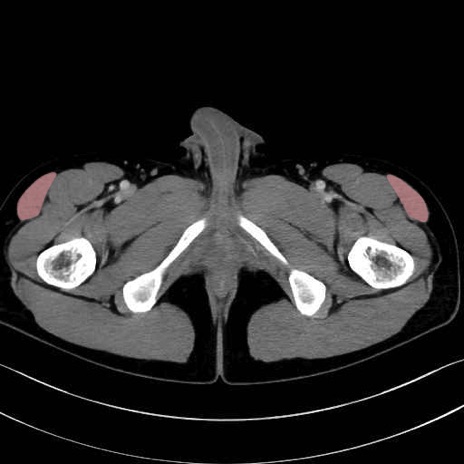

大腿筋膜張筋 (Tensor fasciae latae)